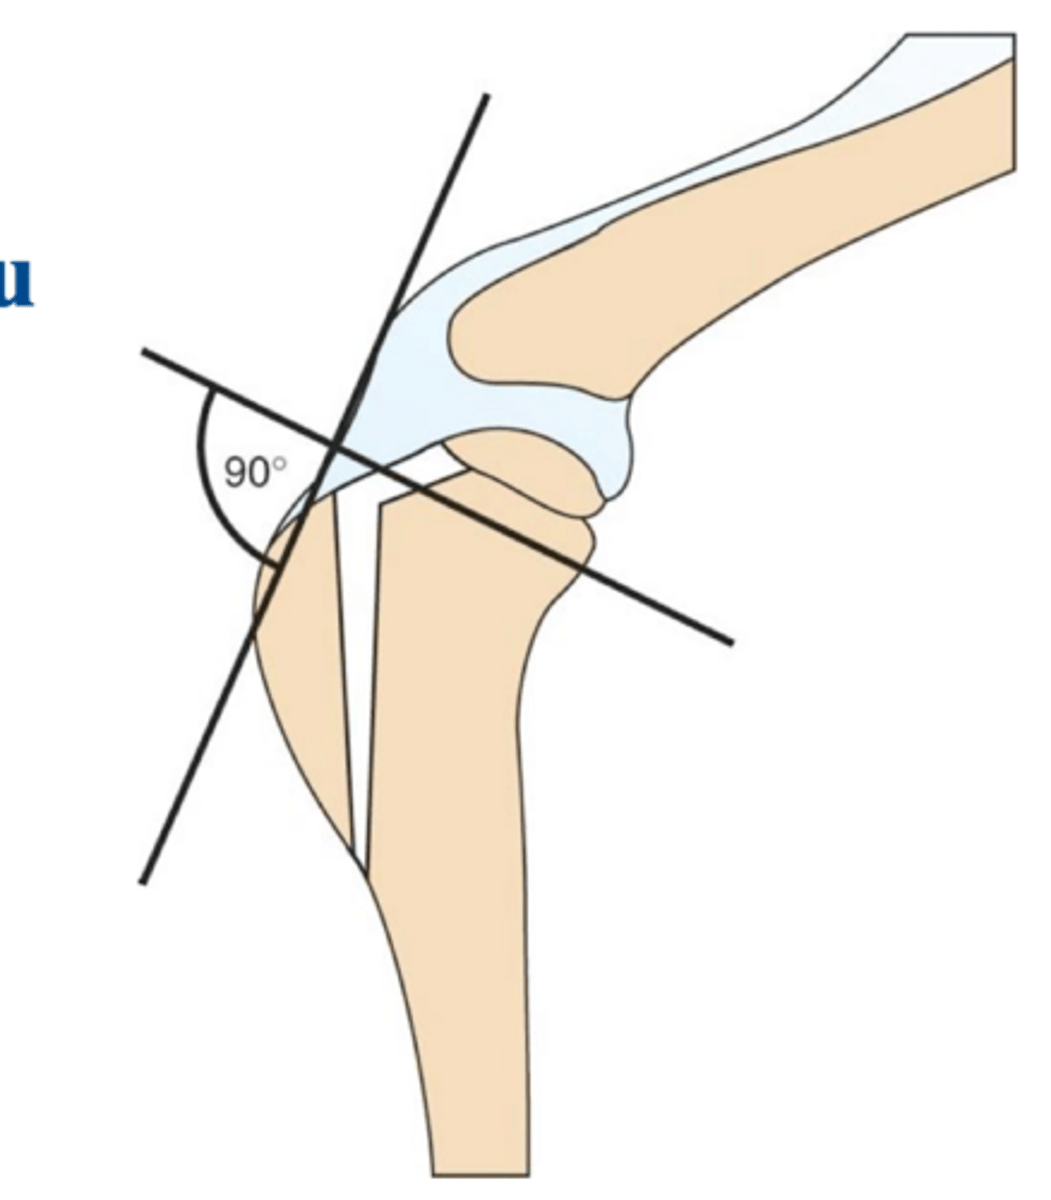

osteotomy of NWB portion of tibia to make tibial plateau 90 degrees to the patellar ligament to stabilize the stifle

general idea of the tibial tuberosity advancement (TTA) procedure **same general idea for TPLO**

1. place patellar lig. 90 degrees to slope of tibial plateau

2. advance insertion of tibial tuberosity in cranial direction

3. eliminate tibiofemoral shear and relieve function of CCL

biomechanics of the TTA procedure